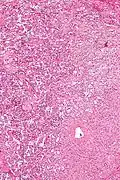

| Micrograph of a gangliocytic paraganglioma. H&E stain. | |

A gangliocytic paraganglioma is a rare tumour that is typically found in the duodenum and consists of three components: (1) ganglion cells, (2) epithelioid cells (paraganglioma-like) and, (3) spindle cells (schwannoma-like).[1]

GP consist of three components (1) ganglion cells, (2) epithelioid cells (neuroendocrine-like), and (3) spindle cells (schwannoma-like). The microscopic differential diagnosis includes poorly differentiated carcinoma, neuroendocrine tumour and paraganglioma.[1]